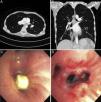

Una mujer de 44 años de edad que presentaba malnutrición, miopatía por desuso y malnutrición, y síndrome de activación mastocitaria, acudió a la consulta por empeoramiento de su dificultad respiratoria y tos ocasional durante los 3 últimos meses. La tomografía computarizada (TC) torácica mostró una lesión endobronquial (fig. 1A y B), por lo que se derivó a la paciente para practicarle una broncoscopia. La diarrea persistente e intensa hizo sospechar que la paciente podría presentar un tumor carcinoide endobronquial. La broncoscopia flexible reveló la presencia de un cuerpo extraño en el bronquio intermedio (fig. 1C y D), que se extrajo mediante una cesta metálica. El bronquio intermedio contenía una gran cantidad de tejido de granulación rodeando al comprimido, y se aspiró una copiosa secreción purulenta. El tamaño y el aspecto del cuerpo extraño eran compatibles con los de los comprimidos de citrato de calcio que tomaba a diario; sin embargo, la paciente no recordaba el episodio de aspiración. La aspiración de un comprimido multivitamínico o de calcio solo se ha comunicado en raras ocasiones1,2 debido, posiblemente, al tamaño de este tipo de comprimidos. Se desconoce si un comprimido de calcio puede disolverse de forma espontánea en caso de que el paciente no pueda expulsarlo. En nuestro caso, la elevada densidad radiológica (media: 576UH) y los bordes nítidos del cuerpo extraño sugirieron la aspiración de un comprimido.